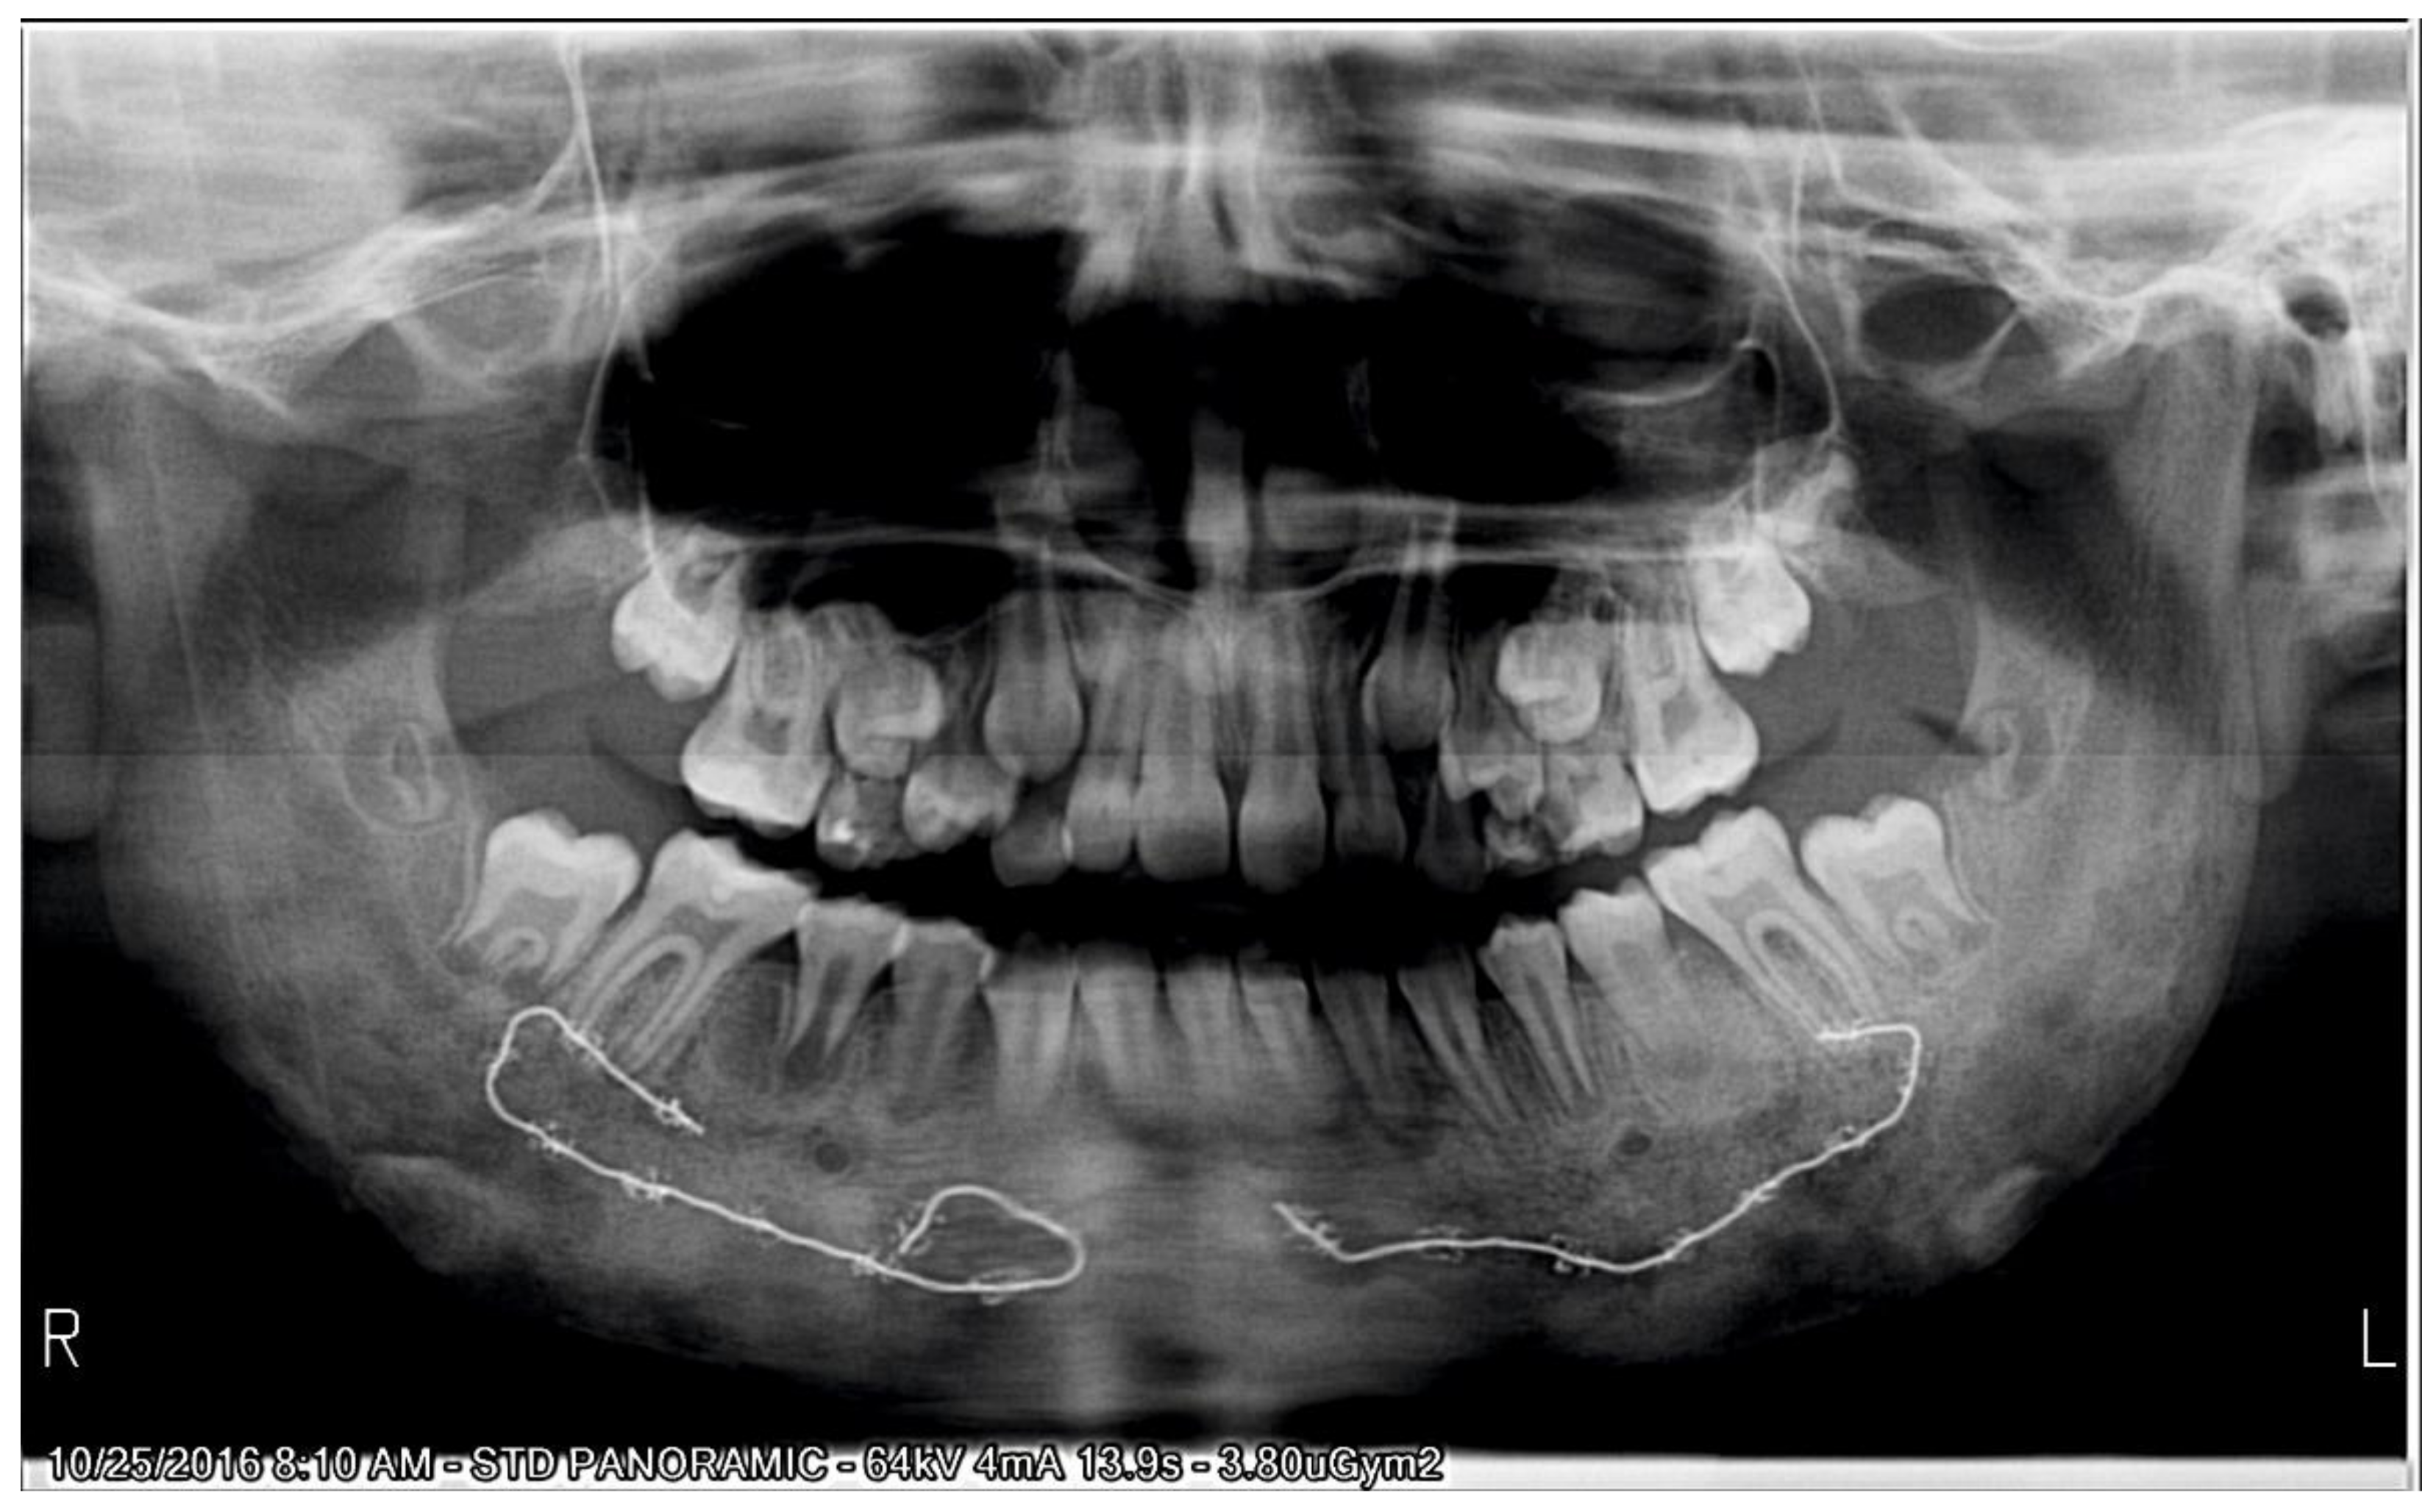

Garre's Osteomyelitis Radiographic Features . The radiographic appearance of periostitis ossificans. In general, the function of the affected bone is preserved. 5 the radiographic features include cortical thickening and loss of medullary canal. Garre's osteomyelitis is a local thickening of the periosteum caused by a slight irritation or infection. Raised inflammatory markers, negative tissue culture and radiological findings in our patient are common features in sclerosing osteomyelitis. Chronic osteomyelitis with proliferative periostitis, known as garre’s osteomyelitis, is a type of osteomyelitis. Apart from the typical onion skin appearance, po shows various other radiographic appearances. Radiological differential diagnosis of po includes infantile cortical hyperostosis, ewing's sarcoma, and osteosarcoma; We aimed to present the extraoral, intraoral, and. None of which fitted the clinical.

Radiological differential diagnosis of po includes infantile cortical hyperostosis, ewing's sarcoma, and osteosarcoma; Garre's osteomyelitis is a local thickening of the periosteum caused by a slight irritation or infection. 5 the radiographic features include cortical thickening and loss of medullary canal. Apart from the typical onion skin appearance, po shows various other radiographic appearances. Chronic osteomyelitis with proliferative periostitis, known as garre’s osteomyelitis, is a type of osteomyelitis. We aimed to present the extraoral, intraoral, and. None of which fitted the clinical. In general, the function of the affected bone is preserved. Raised inflammatory markers, negative tissue culture and radiological findings in our patient are common features in sclerosing osteomyelitis. The radiographic appearance of periostitis ossificans.

Garre's Osteomyelitis Radiographic Features In general, the function of the affected bone is preserved. None of which fitted the clinical. Chronic osteomyelitis with proliferative periostitis, known as garre’s osteomyelitis, is a type of osteomyelitis. 5 the radiographic features include cortical thickening and loss of medullary canal. Radiological differential diagnosis of po includes infantile cortical hyperostosis, ewing's sarcoma, and osteosarcoma; We aimed to present the extraoral, intraoral, and. In general, the function of the affected bone is preserved. Raised inflammatory markers, negative tissue culture and radiological findings in our patient are common features in sclerosing osteomyelitis. The radiographic appearance of periostitis ossificans. Garre's osteomyelitis is a local thickening of the periosteum caused by a slight irritation or infection. Apart from the typical onion skin appearance, po shows various other radiographic appearances.